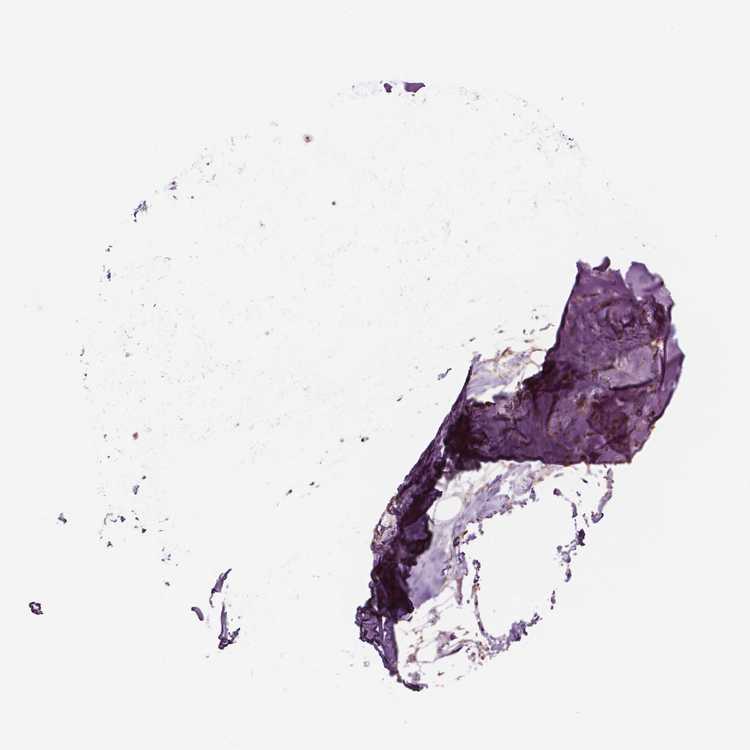

SOFT TISSUE 1 - Antibody stainingi

Antibody staining in the annotated cell types in the current human tissue is reported as not detected, low, medium, or high, based on conventional immunohistochemistry profiling in selected tissues. This score is based on the combination of the staining intensity and fraction of stained cells.

Each image is clickable and will lead to virtual microscopy that enables deeper exploration of all samples and also displays staining intensity scores, fraction scores and subcellular localization as well as patient and tissue information for each sample.

Antibody HPA023314Antibody HPA078682

Fibroblasts Not detectedHigh

SOFT TISSUE 2 - Antibody stainingi

Peripheral nerve Not detected-